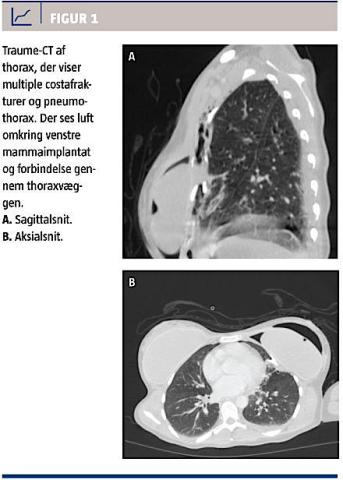

Traume-CT’en viste en mindre pneumothorax, der havde forbindelse med kvindens venstre bryst. Rummet omkring brystimplantatet var luftfyldt, og selve implantatet var deformeret. Derudover fandtes fraktur af costae 2-5 på venstre side, fraktur af venstre sides torakale processus transversus 2 og 3 og fraktur af de torakale processus spinosus på niveau 5-7 (Figur 1).

Ved trafikulykker forekommer der hyppigt stumpe torakale læsioner, som kan medføre traumatisk pneumothorax og ustabil brystkasse (flail chest). Her beskrives et tilfælde, hvor et stumpt thoraxtraume udløste pneumothorax med forbindelse mellem thoraxkaviteten og spalterummet omkring et

brystimplantat.